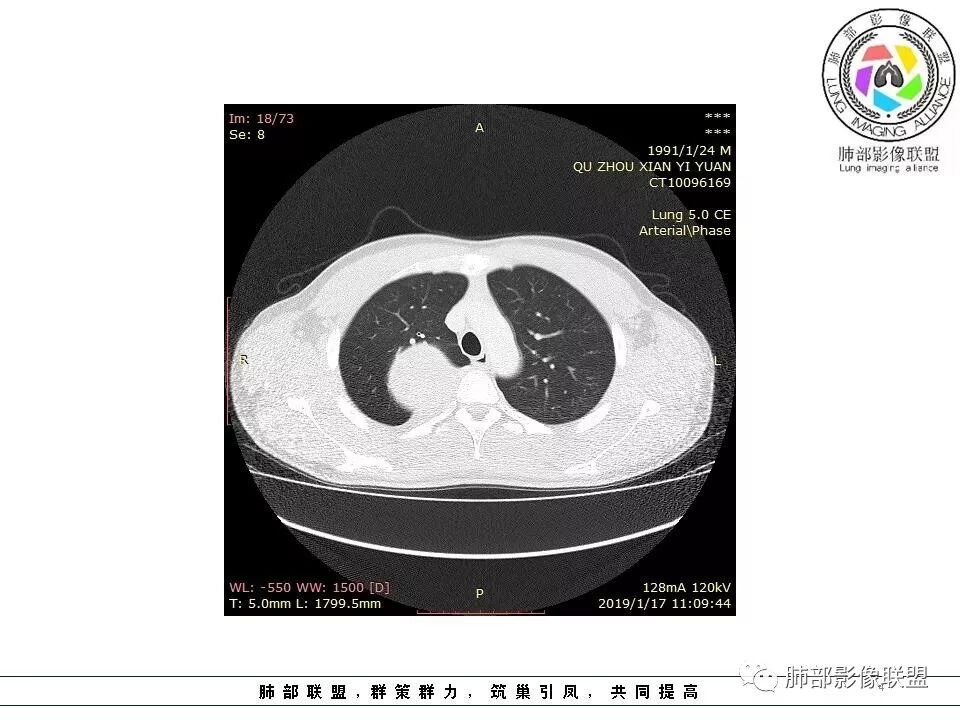

右肺占位,跨越上叶后段、下叶背,边缘光滑,瘤肺界面清,见肺压缩缘(线样不张`强化),见胸膜尾征,胸膜下脂肪未见明显增厚,肋骨丶脊柱未见侵袭及受压,渐进性丶地图样强化,冠状位似见体循环供血

诊断:SFT(来源壁层胸膜?一般小于20%)

鉴别:神经源性(鞘瘤)、LCD、肉瘤丶孤立性间皮瘤

青年男性,瘤肺边界锐利,气管向前推移,定位肺外,局部胸膜增厚,后方见少量积液,提示脏层胸膜来源,增强持续渐渐进性强化,内见蛇纹血管,考虑sft

应该就这两病变鉴别,鞘瘤也可渐进性强化,但鞘瘤囊变多见,内部血管少见不支持

边缘光滑,宽基底与胸壁相连,跨叶裂,叶裂稍前推,血管、支气管前移。

浅分叶

外上侧少量胸水